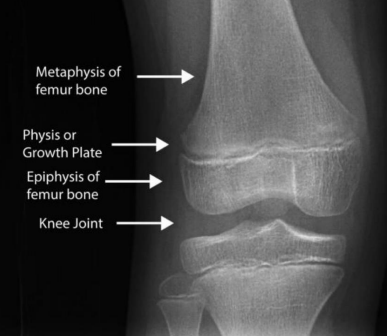

해부1 복습 - 장골(긴뼈)의 구조

- Diaphysis (골간, 뼈몸통) : 긴뼈의 가운데 긴 부분

- Metaphysis (골간단, 뼈몸통끝) : 긴뼈의 양 끝 부분

긴뼈의 구조

Epiphysis (뼈끝)

Metaphysis (뼈몸통끝, 골간단)

Epiphysial plate (뼈끝판) : 성장판(growth plate)

- 성장하면서 점점 길이가 줄어듦

Diaphysis (뼈몸통, 골간) =shaft

뼈끝판(epiphysial plate)의 두께가 두꺼우면 미성숙뼈(immature bone), 얇으면 성숙뼈(mature bone)임.

이 뼈끝판(성장판)은 무기질이 적어, 방사선 사진을 찍으면 X선이 투과하여 빈 공간으로 보임.